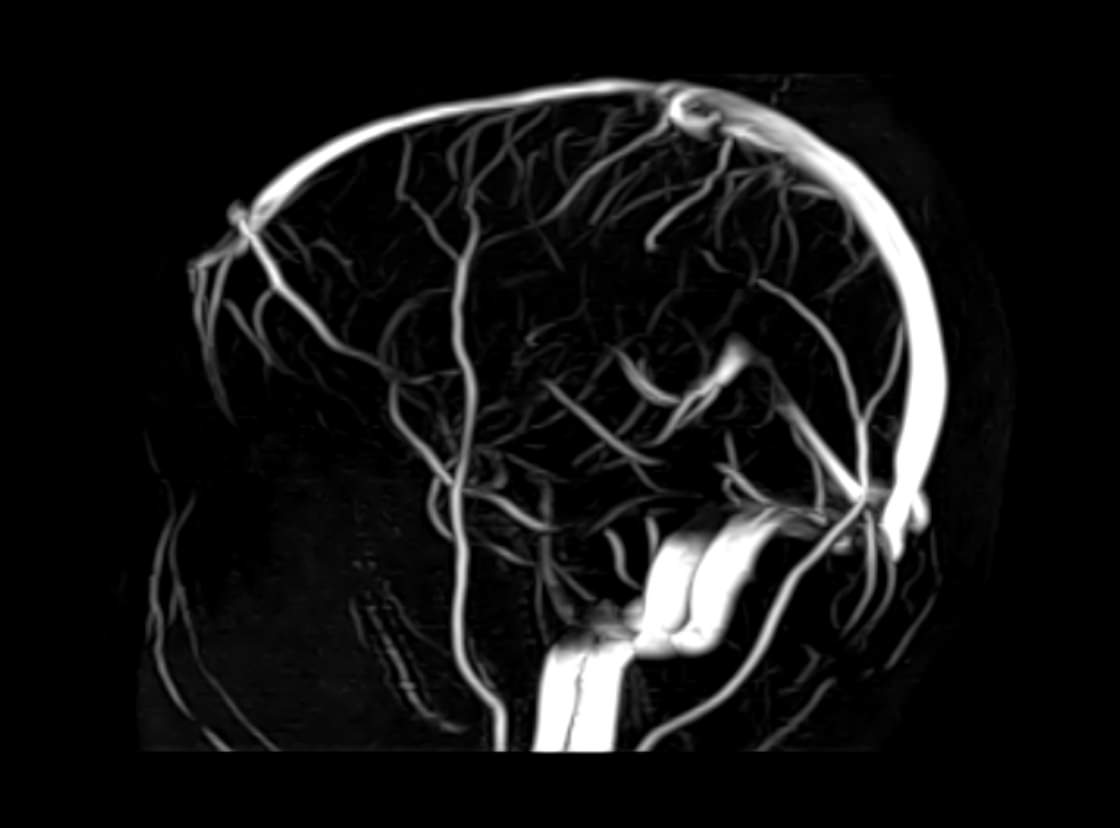

Исследования выполняются на современном высокопольном томографе экспертного класса TOSHIBA VANTAGE TITAN 1,5 Тесла, который использует разные режимы сканирования с толщиной среза от 1мм в различных плоскостях с последующей цифровой обработкой полученных данных для создания трехмерных изображений. МР-ангиография отображает состояние артериальной системы кровоснабжения головного мозга. МР-венография головного мозга позволяет детально изучить особенности венозного русла головного мозга.

Компьютерная программа обрабатывает данные, полученные при сканировании, и формирует объемные изображения как самого мозга, так и сосудистой системы в отдельности без прилегающих тканей. Методики применяются одновременно и взаимодополняют друг друга.

• патология нервов на фоне сосудистых проблем (вазоневральный конфликт — сдавление нерва близлежащим сосудом, также на фоне патологической извитости, аневризмы, сосудистой мальформации).